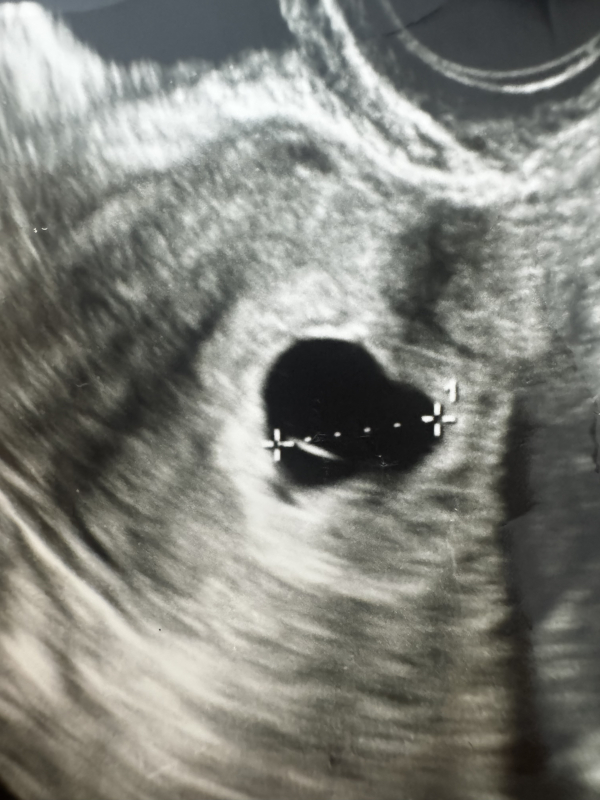

6w4dのエコーです。胎嚢しか見えませんでした。中の白い線はなんでしょうか?

2年ぶりに授かり、1/24に初診に行ったところ、胎嚢13.5ミリしか見えず、胎芽も卵黄嚢も見えませんでした。

胎嚢の中にある白い線はなんでしょうか?

また、右下にぼやけた影があるのは赤ちゃんではないのでしょうか?